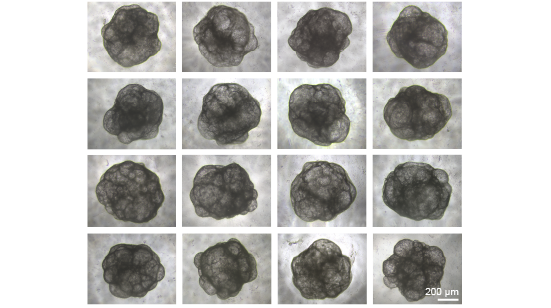

Bright-field images showing the uniform size of liver organoids that generated at day 30 of differentiation from iPSC-U2. Scale bar = 50 μm.